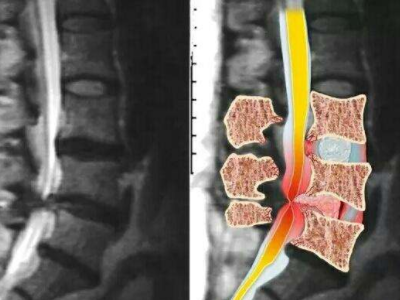

脊柱脊髓神经微创中心以微创技术为引领,以功能恢复为目标,主要治疗脊柱外伤、肿瘤、退行性病变、脊柱畸形等疾病。团队利用神经外科显微技术,结合神经内镜微创技术,对脊柱间盘变性疾病、颈腰椎管狭窄、颈腰椎间孔狭窄、颈腰椎间盘突出、颈腰椎体不稳、脊柱骨折、寰枢椎脱位、脊柱肿瘤、椎管内肿瘤、脊髓损伤、脊髓空洞、脊髓栓系等疾病进行高效、特色手术治疗,如颅颈交界区畸形寰枕减压内固定术、脊柱肿瘤全脊椎切除内固定术、微创椎管内肿瘤切除术、微创脊柱旁肿瘤切除术、寰枢椎脱位椎间融合内固定术、脊柱骨折微创经皮椎弓根钉内固定术、经椎间孔椎间融合内固定术(MIS—TLIF)等,最大程度降低脊柱脊髓手术创伤,具有创伤小、输血少、恢复快、口碑好,出院早等优势。